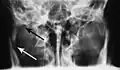

Nondisplaced fracture of the mandible

Plain film radiography

Traditionally, plain films of the mandible would be exposed but had lower sensitivity and specificity owing to overlap of structures. Views included AP (for parasymphsis), lateral oblique (body, ramus, angle, coronoid process) and Towne's (condyle) views. Condylar fractures can be especially difficult to identify, depending on the direction of condylar displacement or dislocation so multiple views of it are usually examined with two views at perpendicular angles.[11]